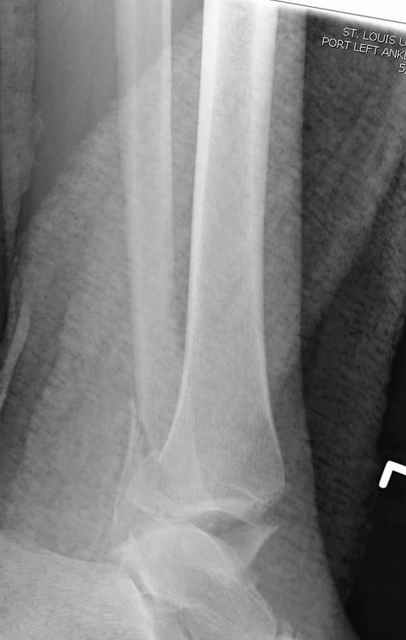

A propos fibular fixation if one is eager to stabilize it separately. In the fracture pattern a way of closed fixation by V-shaped stressed wire (advanced by colleagues from Moscow, prof. Lazarev A.F. et al.) must be excellent. We use indirect closed reduction by the external fixator. Example attached, that fibular fracture is even more suitable for plating but the wire did the job.

Второй случай сделан из одного разреза

Дж